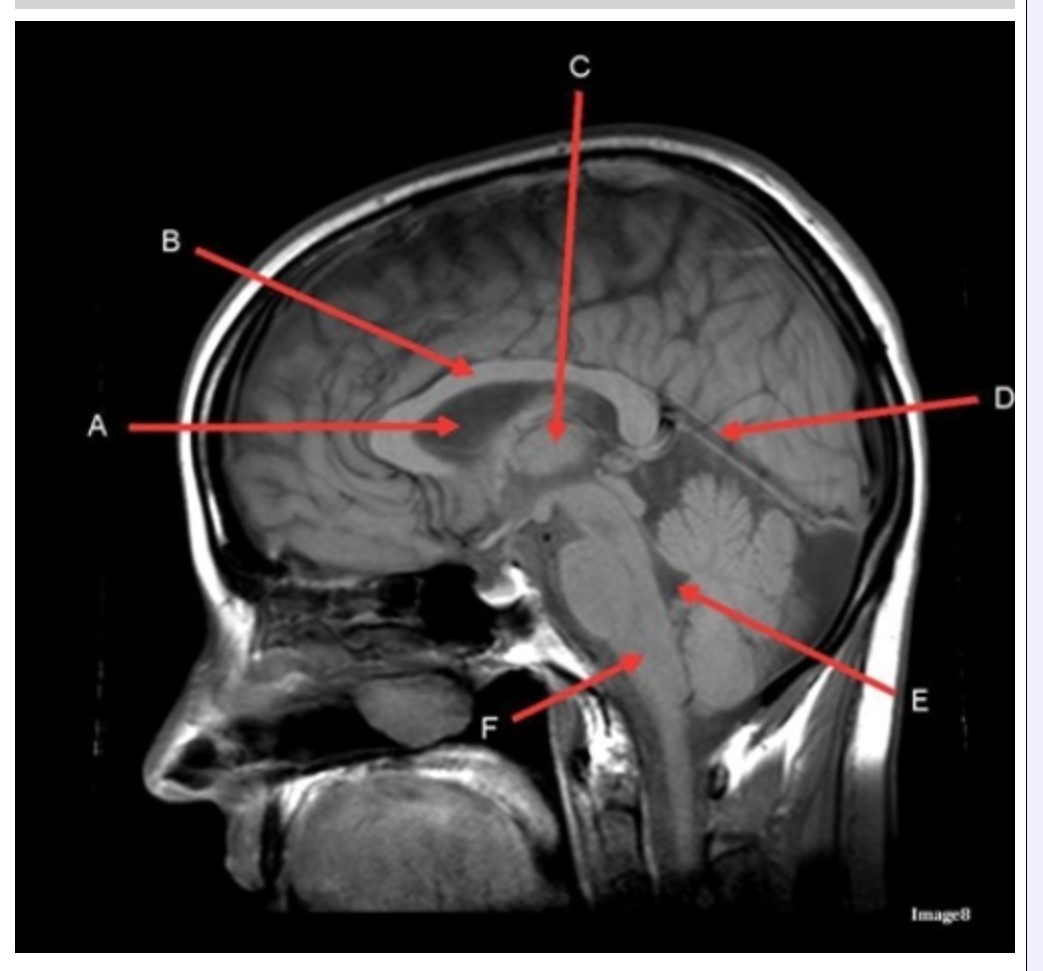

Letter C in Image 8 is pointing to:

A. Tentorium

B. Corpus callosum

C. Thalamus

D. Fourth ventricle

E. Medulla oblongata

Letter F in Image 8 is pointing to:

A. Tentorium

B. Cerebellum

C. Thalamus

D. Fourth ventricle

E. Medulla oblongata

Letter E in Image 8 is pointing to:

A. Tentorium

B. Cerebellum

C. Thalamus

D. Fourth ventricle

E. Medulla oblongata

Letter B in Image 8 is pointing to:

A. Tentorium

B. Corpus callosum

C. Hypothalamus

D. Fourth ventricle

E. Medulla oblongata

Letter D in Image 8 is pointing to:

A. Tentorium

B. Cerebellum

C. Thalamus

D. Fourth ventricle

E. Medulla oblongata

Image 8 is an example of a _______ weighted sequence acquired in the _______ scan plane.

A. T1; Axial

B. T1; Sagittal

C. T2; Axial

D. T2; Sagittal